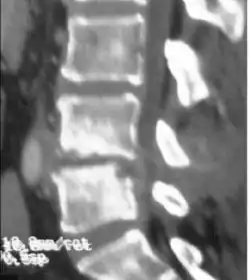

Diagnosis is usually apparent on MRI although plain X-rays and CT examinations can be suggestive. The MRI will reveal air changes in the disc and possibly even external involvement involving the bone or epidural regions. A biopsy may be performed and helps with diagnosis in some cases but often an organism is not obtained. C-reactive protein levels and ESR levels will be elevated and are useful for treatment. Often, the white blood cell count will be normal and the patient will be afebrile.